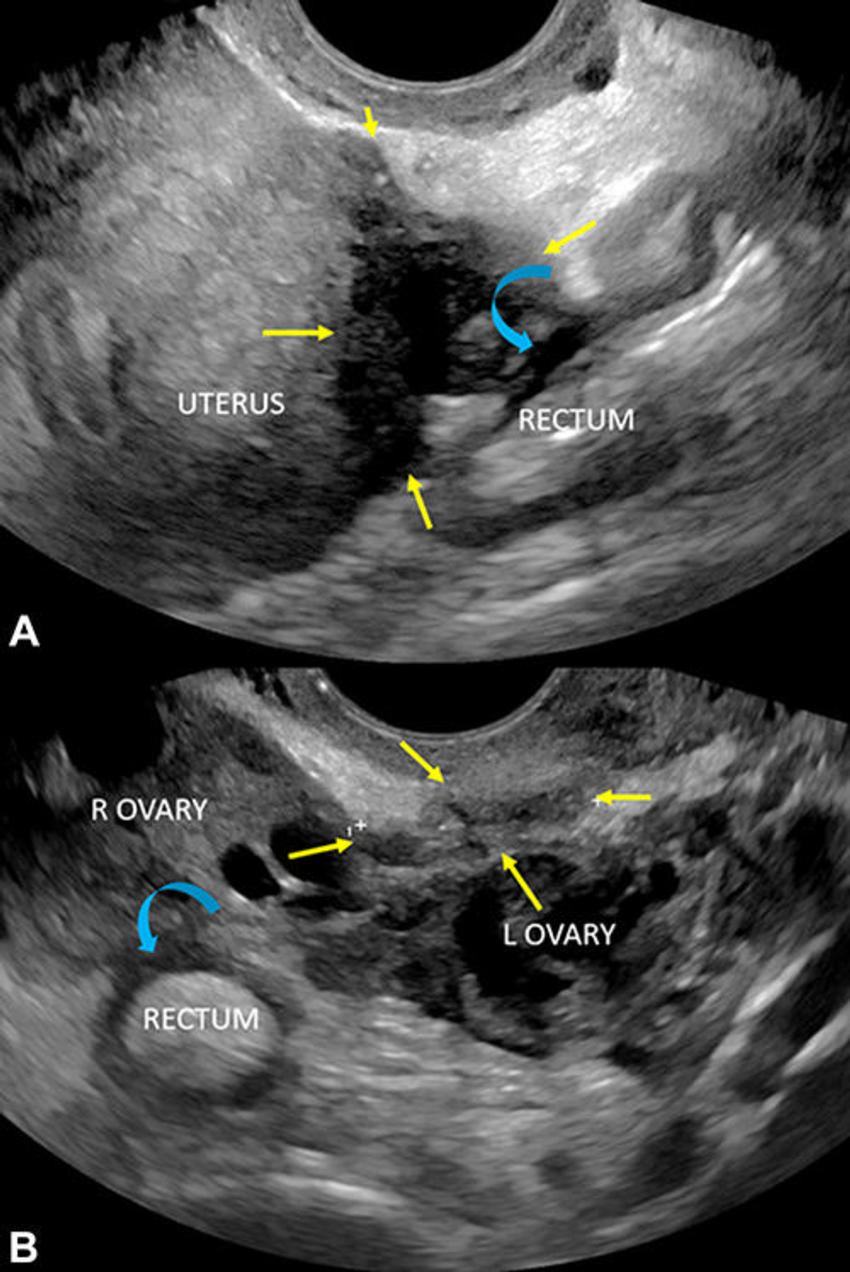

Figure 5. Transvaginal US through the posterior fornix in a 43-year-old patient with deep dyspareunia. Serosal adhesions to the adjacent rectum are shown (curved blue arrows). (A Longitudinal and B) transverse views show kissing ovaries without endometriomas, a category B (indirect endometriosis) observation. Deep endometriosis of the torus uterinus and posterior uterine serosa is shown (yellow arrows, A and B), a category A (direct endometriosis) observation. L = left, R = right.